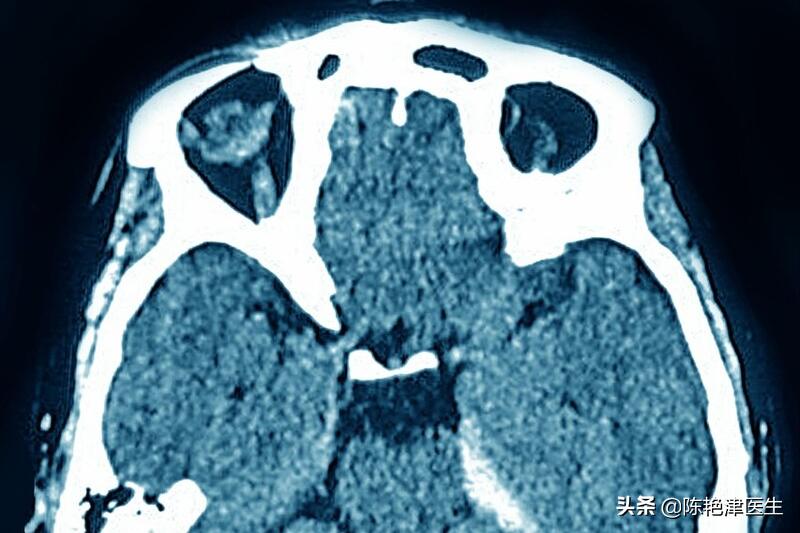

脑出血起病急骤、病情凶险、死亡率非常高,是急性脑血管病中最严重的一种,为目前 我国中老年人死因顺位第一 ,且仍逐年递增8.7%。每年冬季,各大医院收治的脑出血患者人数就明显增加。

脑出血是由多种原因引起的非外伤性的脑实质出血,是临床常见的急症之一,其发病原因主要与脑血管的病变有关。患者往往由于 情绪激动、费劲用力时突然发病 ,早期死亡率很高,即使抢救回来的幸存者,其中多数也会留下不同程度的后遗症,如运动障碍、认知障碍、言语吞咽障碍等,后果十分严重。

脑出血常在活动或情绪激动时发病,在发生脑出血的患者中, 50%有先兆症状 , 一般有头痛和呕吐,并迅即出现昏迷、偏瘫、大小便*禁失**等症状 ,出血部位不同表现也不同。其中剧烈的头痛是脑出血的最常见症状,脑出血的最初5分钟,对于生命至关重要; 准确快速的家庭急救可以阻止疾病的发展,降低病死率和致残率,对脑出血病人预后也具有十分重要的意义[1]。